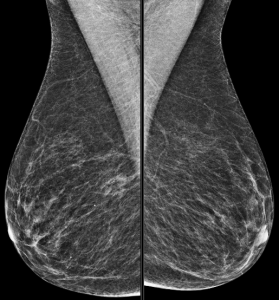

Magnification views were performed for the right breast calcifications seen on a screening mammogram:

Explanation: These are the large, coalescent, coarse or “popcorn-like” calcifications that are typical of an involuting fibroadenoma.

There are actually probably two or three adjacent fibroadenomas in this location. The dominant large calcification represents the end stage of an entirely calcified involuting fibroadenoma. The smaller adjacent popcorn-like calcifications represent an earlier stage of involution in a different fibroadenoma.